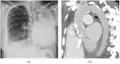

Fibrothorax on chest x-ray | |

Diagnostic method | Chest X-ray, CT scan |

A fibrothorax can typically be diagnosed by taking an appropriate medical history in combination with the use of appropriate imaging techniques such as a plain chest X-ray or CT scan.[3] These imaging techniques can detect fibrothorax and pleural thickening that surround the lungs.[7] The presence of a thickened peel with or without calcification are common features of fibrothorax when imaged.[3] CT scans can more readily differentiate whether pleural thickening is due to extra fat deposition or true pleural thickening than X-rays.[3]

If a fibrothorax is severe, the thickening may restrict the lung on the affected side causing a loss of lung volume.[7] Additionally, the mediastinum may be physically shifted toward the affected side.[3] A reduction in the size of one side of the chest (hemithorax) on an X-ray or CT scan of the chest suggests chronic scarring.[6] Signs of the underlying disease causing the fibrothorax are also occasionally seen on the X-ray.[6] A CT scan may show features similar to those seen on a plain X-ray.[7] Lung function testing typically demonstrates findings consistent with restrictive lung disease.[6]